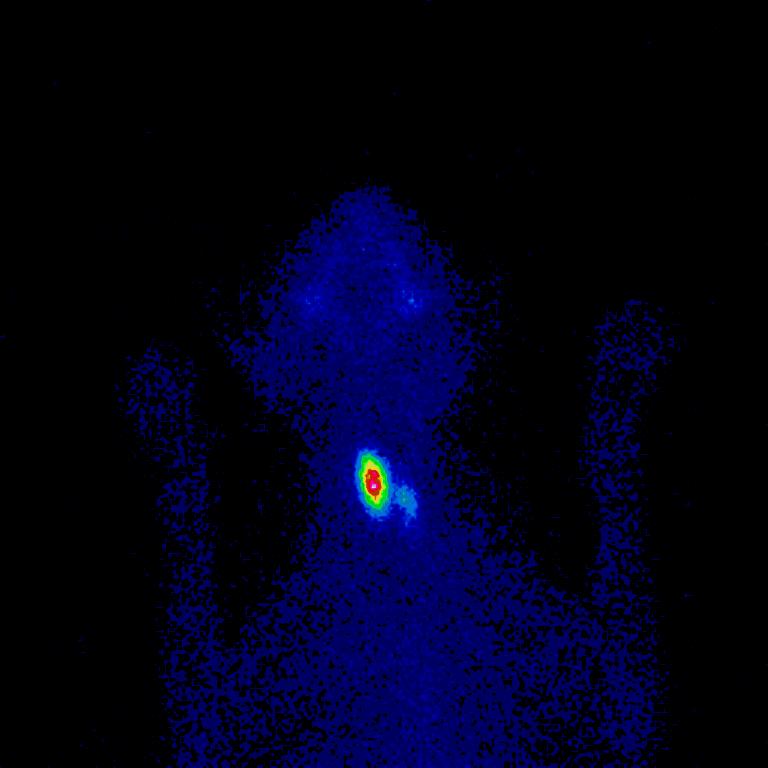

Voor een behandeling van hyperthyreoïdie met radioactief jodium is het belangrijk om te weten of een schildklier echt overactief is én waar dat schildklierweefsel zich bevindt. Door het inspuiten van een radioactieve stof (technetium) worden de overactieve cellen van de schildkliertumor zichtbaar gemaakt met behulp van een schildklierscan. Zo weten wij precies waar het overactieve weefsel zit in de kat.

De eerste dag van de therapie wordt een schildklierscan gemaakt, ook wel scintigrafie genoemd. Daardoor kunnen wij via een gammacamera zien waar het actieve schildklierweefsel zit. Aan de hand van deze schildklierscan kunnen wij beoordelen of er sprake is van een kat met hyperthyreoïdie en welke hoeveelheid radioactief jodium gegeven moet worden. Eventuele aanvullende onderzoeken kunnen dan in overleg met u worden gedaan.